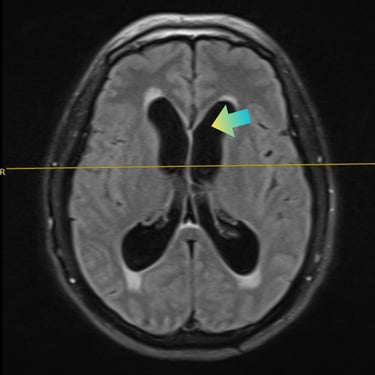

La hidrocefalia es una condición caracterizada por la acumulación anormal de líquido cefalorraquídeo en los ventrículos cerebrales, lo que genera aumento de la presión intracraneal y síntomas como cefalea, náuseas, alteraciones cognitivas y trastornos de la marcha. Cuando el manejo médico no es suficiente, la derivación ventriculoperitoneal (DVP) es el tratamiento quirúrgico más utilizado. Este procedimiento permite drenar el exceso de líquido desde el cerebro hacia la cavidad abdominal, donde es reabsorbido, aliviando la presión intracraneal y mejorando la función neurológica. El tratamiento oportuno es clave para prevenir secuelas.